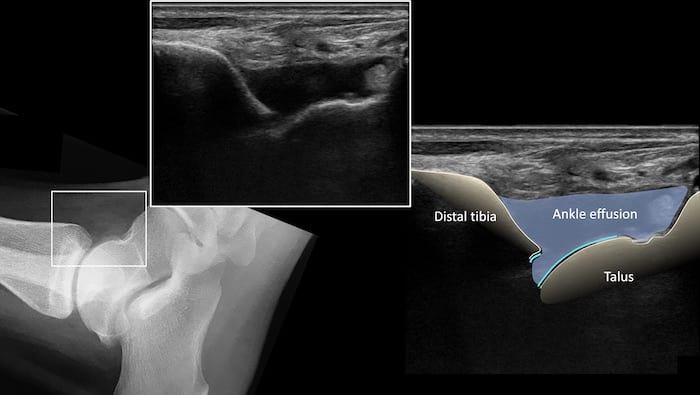

발목 관절낭염 @ LITFL.com

위 그림처럼관절낭에 염증으로물이 찬 경우가 많습니다.뒤쪽이 아프다고전부 아킬레스건의 문제는아닌 것이죠.